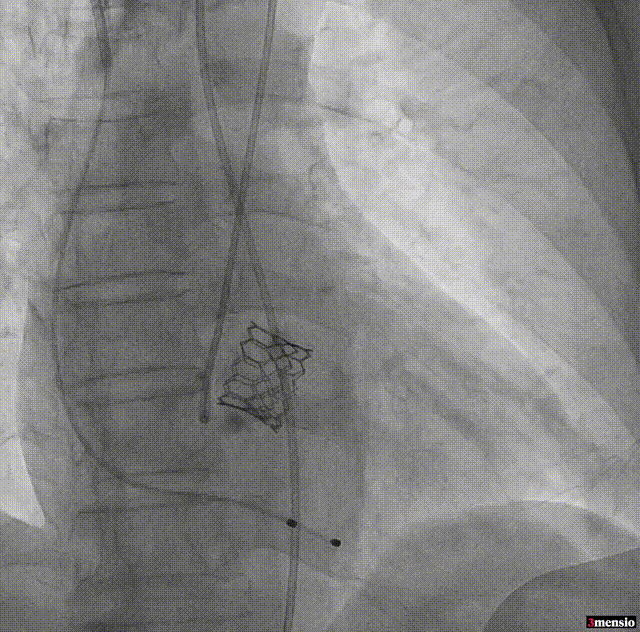

TYPE1型二叶瓣,瓣环面积:359.1mm²,直径:21.7mm;LVOT面积:364.1mm²,直径:22mm;瓣上限制区(瓣上9.2mm)长径:22.4mm,短径:21.8mm;AscAO:45.8mm;左冠高度:11.8mm;右冠高度:14.9mm;心脏角度:68°。

瓣上钙化重,虚拟瓣环、左右交界处及无冠窦侧均有体积大、靠近血管壁且有锐性突出的钙化,选择较大的瓣膜虽然能更好的封堵瓣周漏,但会大大增加瓣环破裂的风险;选择稍小号瓣膜封堵瓣周漏层面较少、容错率相对较低,术后会有残余瓣周漏可能。

主动脉弓降部走行成锐角、弓顶部可见少许钙化,横位心68%伴有升主动脉扩张。